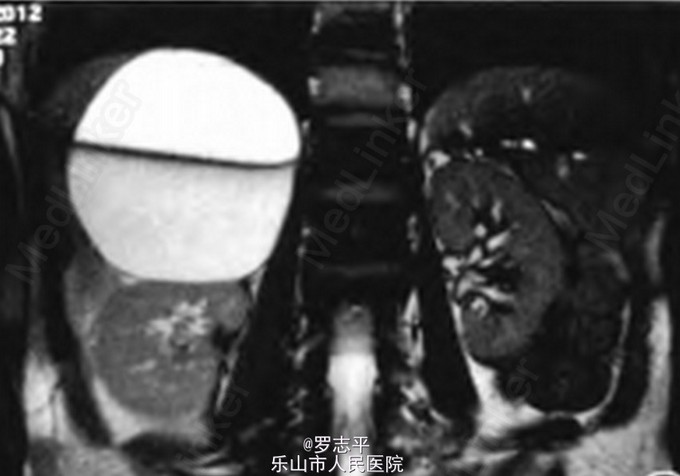

彩色多普勒超声检查示右肾上腺区有一10.2 cm×9.2 cm的囊性结构,内见分隔,周边可见钙化。MRI示检查右侧肝肾间隙有一约11.0 cm×l0.0 cm×7.3 cm巨大肿物,边缘清晰,包膜完整,内可见分隔,考虑囊肿

术后病理诊断:囊壁由纤维、脂肪组织组成,其内可见钙盐沉积,结合临床符合肾上腺假性囊肿。随访近8个月,复查彩色多普勒超声未见囊肿复发。 肾上腺囊肿属于良性病变,临床少见,尸检发病率为0.064%~0.180%。多发于中青年,女性发病率略高,多为单侧发病,两侧无明显差别。 本例为假性囊肿,组织上可见纤维组织形成的囊壁,囊壁可见钙化斑,囊液常为新鲜血性或陈旧性血性。肾上腺囊肿通常无特征性临床症状和体征,大多于体检中被发现。部分较大的囊肿可有邻近器官非特异性的压迫症状。影像表现与邻近器官无明显界限。肾上腺慢性出血性囊肿形态较规则,出血吸收可引起含铁血黄素沉着,囊内容物如本例所示呈浑浊、棕褐色液体;影像上形成典型的液一液平面,如本例MRI影像。激素检查对所有肾上腺囊肿患者均为必需,以便排除临床症状不明显的功能性疾病。 本例患者的激素检查均无异常。